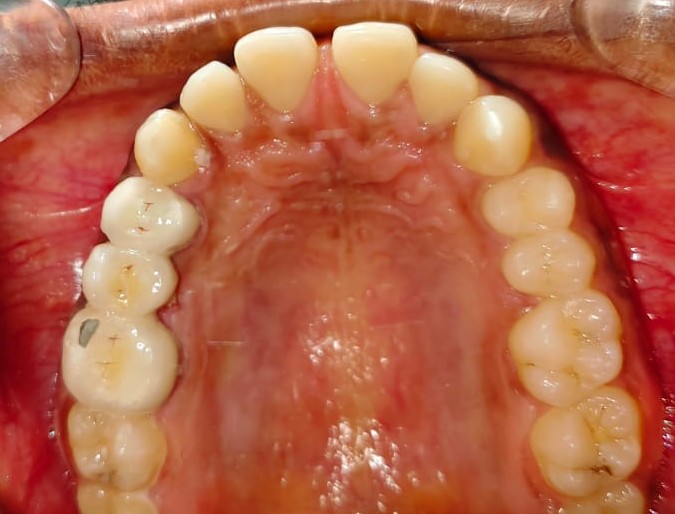

After/Before

See stunning smile transformation before and after

Before After